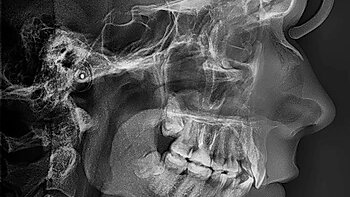

ТРГ- телерентгенограмма, стандартный 2-х мерный рентгеновский снимок, назначаемый в основном стоматологами-ортопедами, челюстно-лицевыми хирургами и травматологами. Снимок можно произвести в двух основных проекциях, прямой и боковой, в зависимости от того, что именно хочет увидеть врач. На снимке ТРГ можно увидеть не только костную, но и мягкие ткани, что позволяет лучше составить программу лечения в ортодонтии. Для чего нужен снимок ТРГ: ...

Проект «Медилайт» пришел в компанию в феврале 2023 года. Тогда, по совету одного из наших клиентов, в компанию «ТЛТ ПРО» обратился диагностический центр с одноименным названием. В нашей сегодняшней статье мы расскажем о проекте по разработке сервиса автоматического расчета ТРГ для рентгенодиагностического центра «Медилайт». Что такое «Медилайт»? «Медилайт» — это современный диагностический центр, который занимается двухмерными и трехмерными исследованиями челюстно-лицевой области. Врачи центра делают...